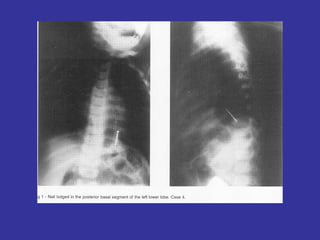

FOREIGN  BODY  ASPIRATION Children often ingest or aspirate a foreign body, with variable outcomes. Missed or late diagnosis may lead to serious morbidity or death. Children will put almost anything they find into their mouth; like food (peanuts, grapes, candy, hot dog),  batteries, buttons, coins, crayons, jewelry, marbles, paper clips, pen caps, pins, screws, toy parts,  chicken or fish bones. History:  Most ingestions and aspirations of a foreign body occur in a normal child in their home, under their parents care.  Poor safety proofing; unattended child, running with food,   or handling a small object  It’s a toddler with a sudden onset of cough, choking, persistent wheezing, gags, and vomits at the time  of ingestion Peak age:  6 months-4 years Pathology: Usually foreign object lodge  below the carina.   In toddlers, lodge in either mainstem In older children, they lodge in the  Right mainstem

S/S:   Acute: Coughing, Gagging, Choking, Wheezing (localized)  Chronic: asymmetrical/absent breath sounds, recurrent pneumonia Most common object:  Peanut,   then  Candy, coins, grapes, Hot Dog  CXR:   Lower Airway Area: Unilateral hyperinflation, Air trapping on  affected side.  Atelectasis Mediastinum shift  AWAY   from affected side/atelectasis Esophageal area: lodged at one of these locations: Thoracic inlet Level of aortic arch and left mainstem bronchus  Gastroesophageal junction,. CT scanning supplemented with virtual bronchoscopic imaging may further provide such useful information prior to an attempt at bronchoscopy TX:   Removal by Rigid bronchoscopy, under anesthesia Inhalation to relieve bronchospasm following removal Complications:   Aspiration Pneumonia, Lung abscess